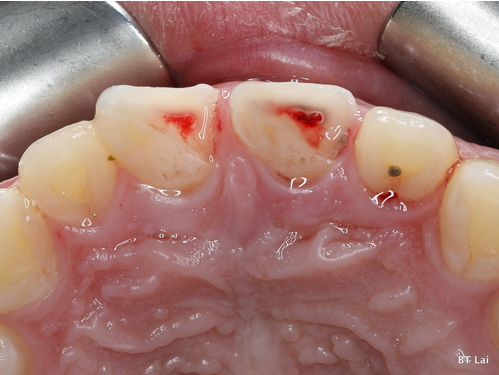

7歲孩童小松是在一年半前不小心把上顎新萌發的恆齒撞斷,經急診醫師會診根管治療科賴博堂主任接手以活髓治療。現在的小松雖然偶爾會因咬到堅硬的食物而使黏上去的斷片掉落,需再重新黏上之外,整顆牙仍保留恆齒成長潛能。

左圖:7歲孩童小松是在一年半前不小心把上顎新萌發的恆齒撞斷,圖為術前影像2。(賴博堂提供)